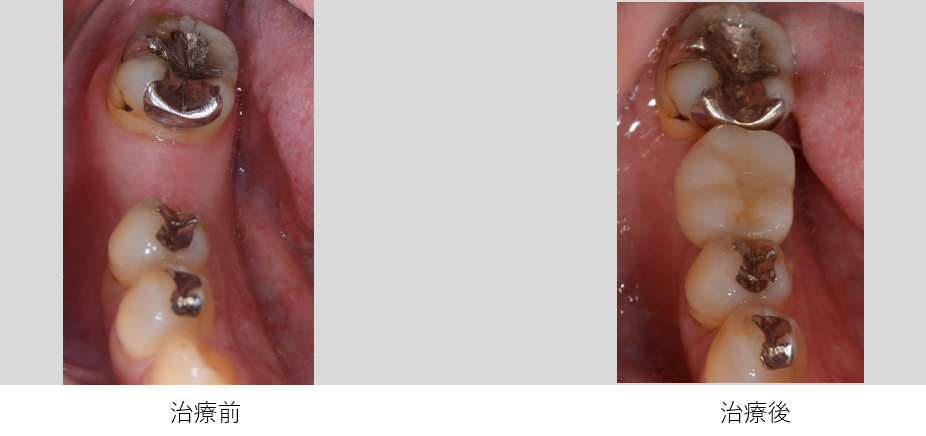

ケース2

| 年齢・性別 | 54歳・女性 |

| 主 訴 | 被せ物が合わないのでやりかえたい |

| 治療部位 | 右下6番 |

| 治療期間 | 6ヶ月 |

| 治療費 | インプラント審査診断:55,000円 インプラント体埋入:165,000円 上部構造(ジルコニアステインクラウン):165,000円 合計385,000円 (2023年7月現在) |

| 治療内容 | 右下5番6番 インプラント埋入、GBR、FGG、インプラントTEK、インプラント上部構造(ジルコニアステインクラウン)、サージカルガイド |

| 治療の リスク |

天然の歯と比較すると歯ぐきのトラブルが生じやすい 天然歯の歯ぐきには細菌の侵入を防ぐための線維のバリアが存在していますが、インプラントには線維のバリアが存在しません。 そのため、インプラント周りの歯ぐきや骨は細菌感染を起こしやすいと言えます。 しっかりとしたメンテナンスをしないとインプラント周囲炎になり、最悪の場合はインプラントを撤去する必要が生じます。 |

| 治療方針 | 初診時に右下6番は、歯の根が割れているので保存不可と診断しました。その後右下6番は抜歯を行いました。抜歯後しばらく欠損の状態でしたが、右上6番の挺出(※1)が認められた為、インプラント治療を行うことになりました。 骨造成は行わずに埋入手術を行いました。埋入手術から3ヶ月後に上部構造の型どりを行いました。そして手術から5ヶ月程で上部構造の装着をしました。 骨造成を行わないことで外科手術が最小限に抑えられ、治療期間を短く終えることができました。 ※1:挺出 かみ合う歯がなかったり、隣の歯がなかったりする事が原因で、歯が本来あるべき場所から突出してしまったり、移動してしまう事 |

| 特記事項 | 抜歯後しばらく時間が空いていたので、骨と歯ぐきが失われ、抜いた場所は歯ぐきが凹んだ状態になります。 本来であれば骨造成(GBR)を行い、失われた骨を再建した方が、歯ブラシがしやすい歯ぐきとなりセルフケアがしやすくなります。 |

| メンテナンス担当者所見 | 天然歯と比較して、インプラントの上部構造は根元の部分に汚れが溜まりやすい構造となっています。 また、今回骨造成を行わなかったので、通常よりも歯ぐきが凹んだ状態になり、汚れが溜まりやすくなっています。 そこでセルケアではルシェロ歯ブラシI20の使用を提案しました。インプラントと隣在歯の間は、歯間ブラシを使用してケアを行っています。 |